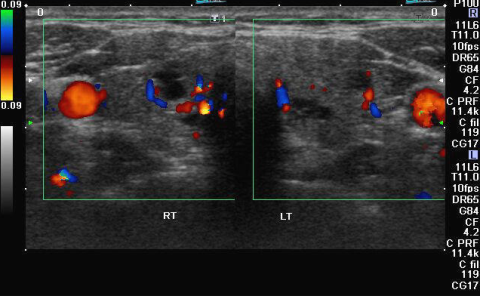

At Ultracare Diagnostic, we understand the importance of your health and the essentiality of accurate diagnosis. Therefore, we offer you comprehensive care and a non-invasive Ultrasound test that helps determine how well your body organs are functioning and if there are any abnormalities present. This helps the doctor to provide you with an accurate diagnosis and treatment for the same

We offers Best Services With Experienced hand on Sonology